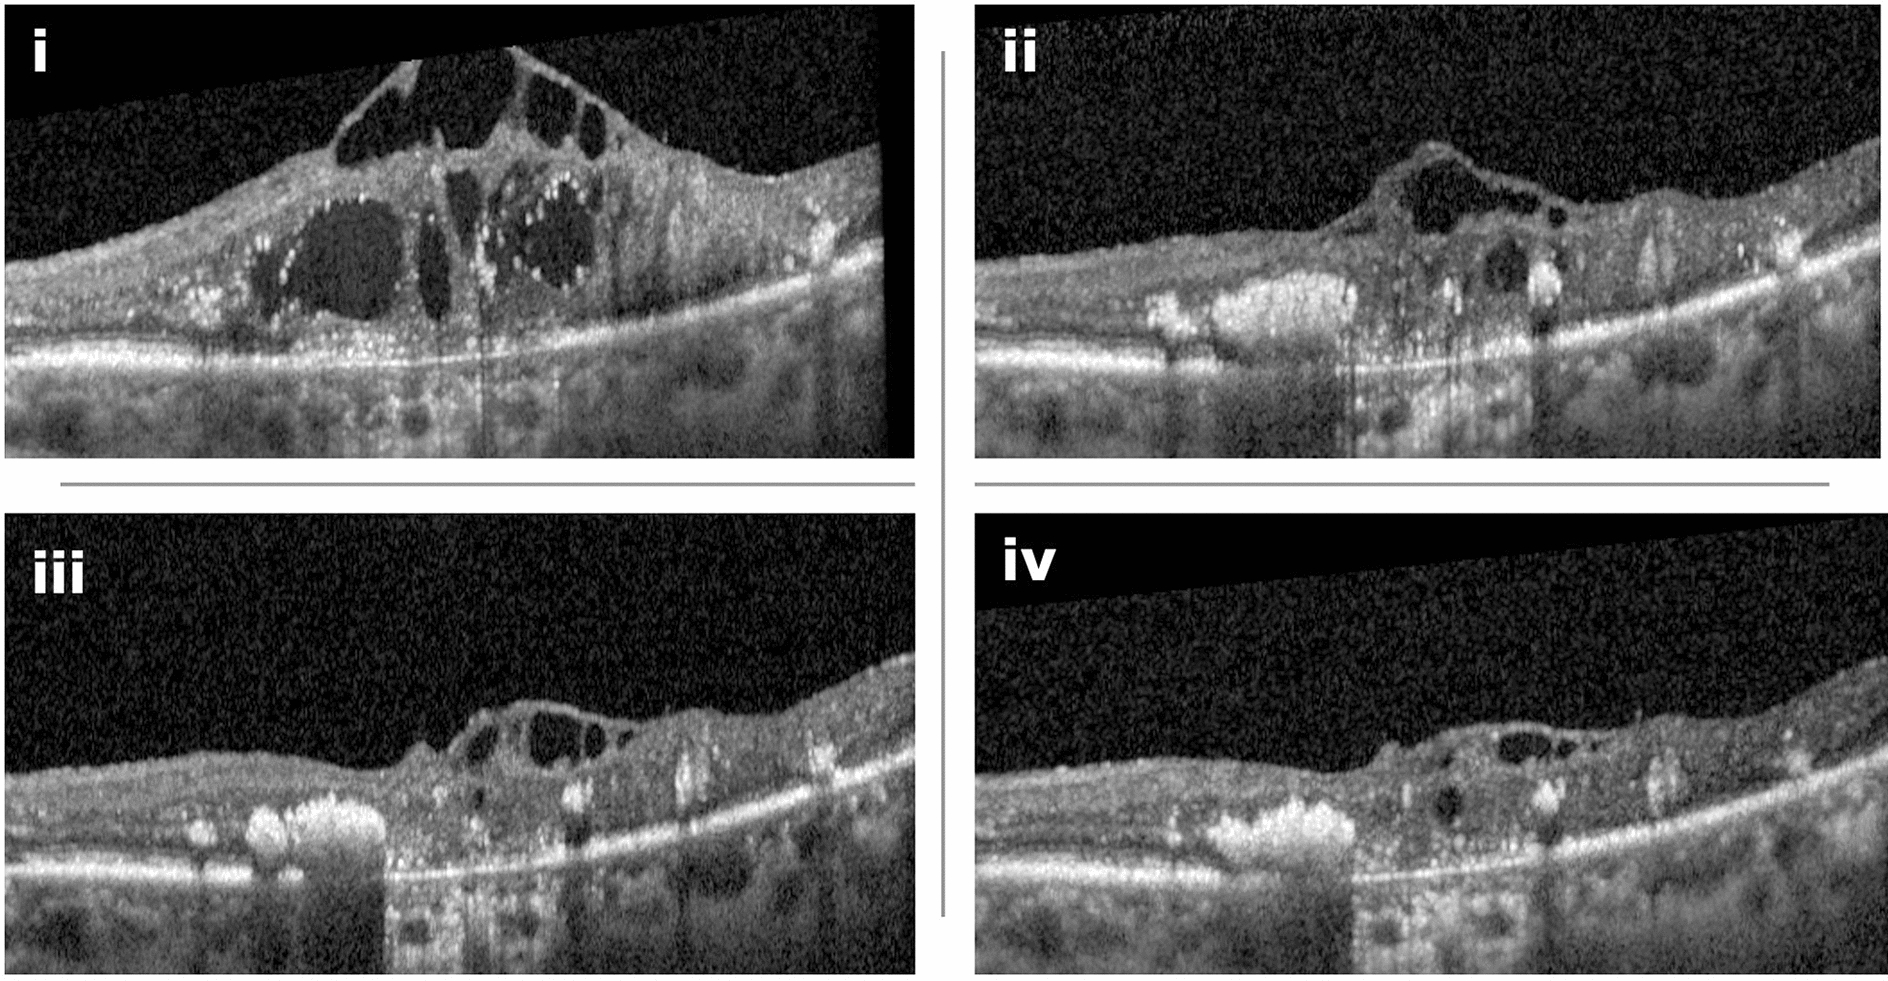

Clinical examples of reduction in CST in OCT scans in two patients are given in Fig. 2 and in Fig. 3.

Fig. 2

Example of a 74-year-old female patient who had received 24 intravitreal anti-VEGF injections prior to switching to faricimab. (i) Optical coherence tomography (OCT) scan before the switch shows pronounced diabetic macular edema (DME) with intraretinal fluid (IRF) and central photoreceptor layer and retinal pigment epithelium disruption, indicative of advanced retinal damage. (ii) One month after the first faricimab injection, there is a strong morphological response. (iii) Following the second injection, further gradual improvement in retinal morphology is observed, with a continued decrease in IRF. (iv) After the third injection, the OCT shows stable findings with minimal residual edema. Despite the anatomical improvement, visual acuity remains limited due to pre-existing, irreversible central retinal atrophy